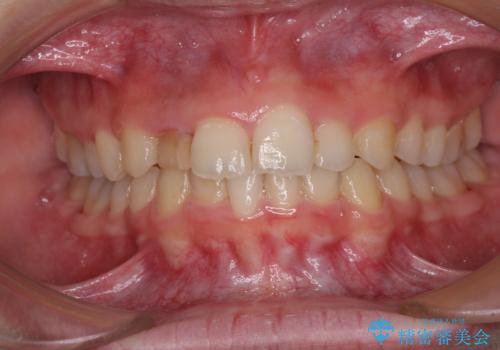

- 前歯の歯並びと不自然な色をした前歯のクラウンを気にして来院された患者様です。

上下前歯の歯列不正はインビザラインにより歯列を整え、その後に、前歯をオーダーメイドタイプのオールセラミッククラウンにて補綴治療することとしました。

前歯のデコボコを一番気にしていらっしゃいましたが、矯正治療により下顎前歯が隠れるほどのディープバイトも一緒に改善され、奥歯に負担のかかりにくい咬み合わせとなりました。